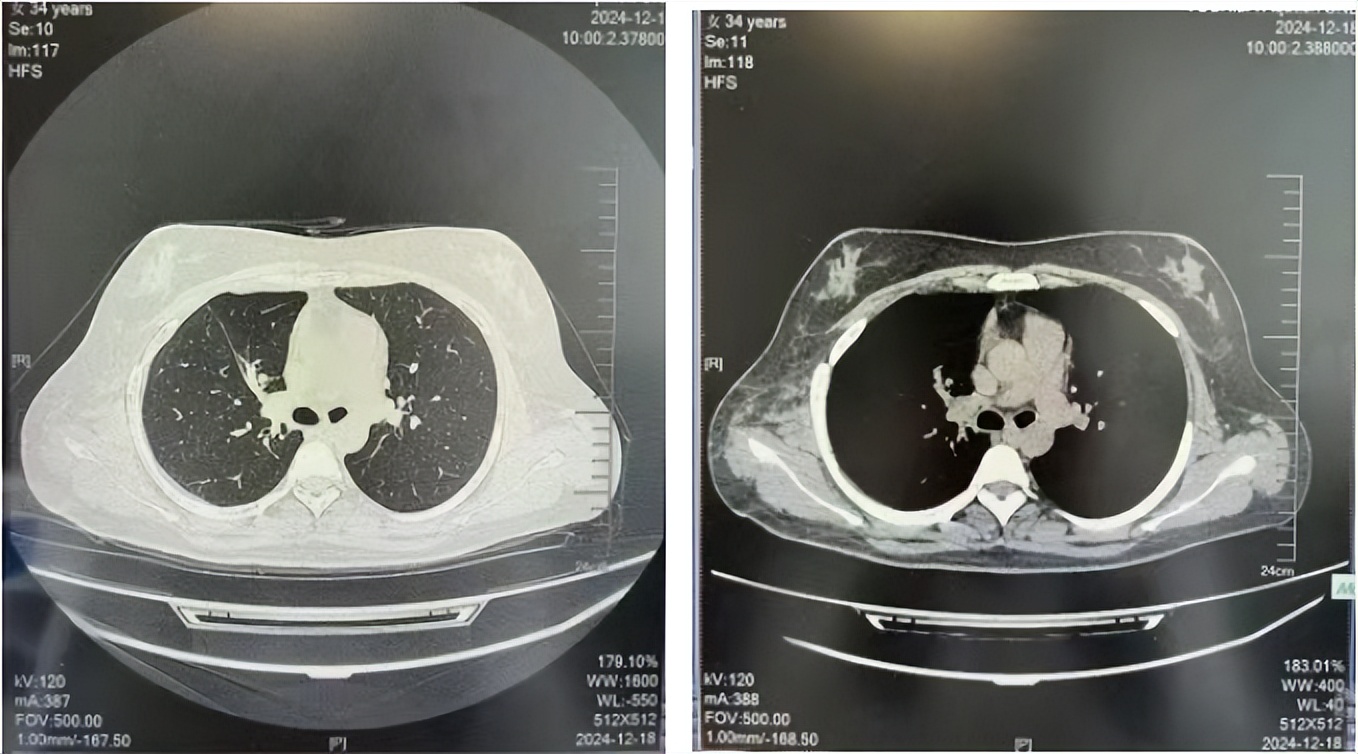

治疗经过:2023年3月27日始行恩沙替尼靶向治疗至今,最佳疗效为PR,末次评效为维持PR。期间出现轻度肝功能异常(DILI 1级),对症处理后好转。截止目前PFS为26个月。

2024年6月复查PR(最佳疗效)

2024年12月复查维持PR

2025年3月复查维持PR